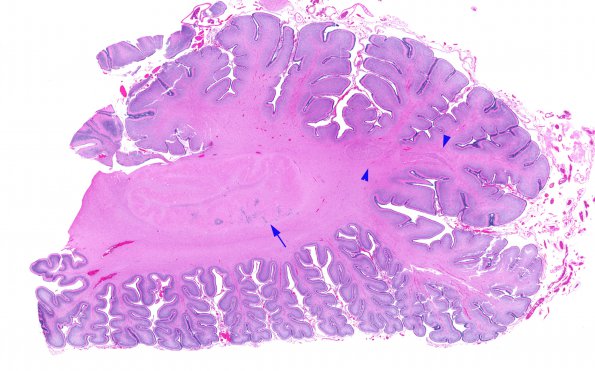

Washington University Experience | DEVELOPMENTAL MALFORMATIONS | Malformation - Cerebellum | 8A1 Heterotopia, cerebellum (Case 8) H&E whole mountA

The cerebellar hemispheres had several forms of maldevelopment including collections of wispy immature granule cell collections involving the otherwise normal dentate nucleus (arrow) and heterotopia (arrowhead)